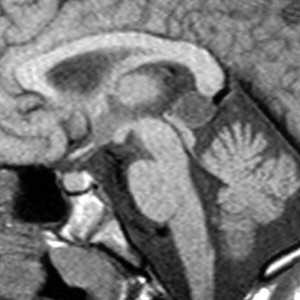

МРТ головного мозга. Сагиттальная Т1-взвешенная МРТ. Пинеальная киста.

Пинеальная киста расположена в проекции шишковидной железы. Встречается с частотой 4-11%. Размеры обычно не превышают 1 см, но изредка встречаются больших размеров. В таких случаях она вызывает окклюзионную гидроцефалию. При головного мозга она имеет все признаки кисты с примесью белка в жидкости, то есть немного светлая на Т1-взвешенных. Изредка встречается геморрагическое содержимое. Киста может контрастироваться по периферии.

Пинеальная киста расположена в проекции шишковидной железы. Встречается с частотой 4-11%. Размеры обычно не превышают 1 см, но изредка встречаются больших размеров. В таких случаях она вызывает окклюзионную гидроцефалию. При МРТ головного мозга она имеет все признаки кисты с примесью белка в жидкости, то есть немного светлая на Т1-зависимых МРТ. Изредка встречается геморрагическое содержимое. Киста может по усиливаться периферии при МРТ головного мозга с контрастированием.

МРТ головного мозга. Т1-взвешенная сагиттальная МРТ. Пинеальная киста.